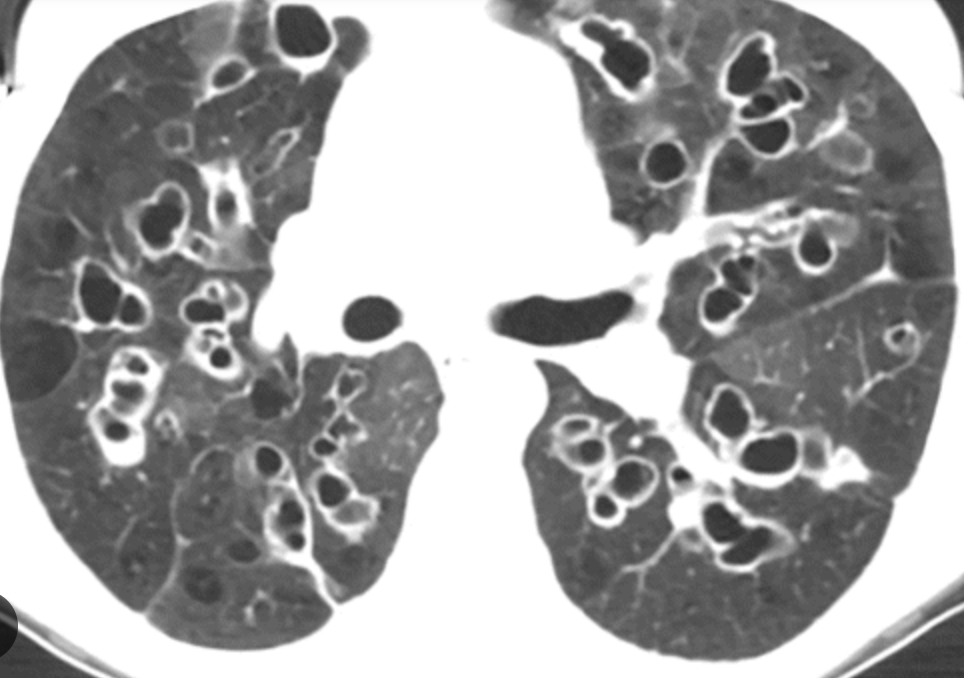

• Projects: Clinical research CF/bronchiectasis and NTM